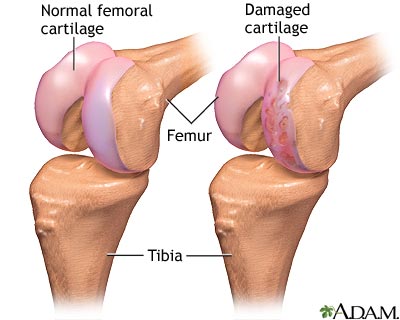

Partial knee replacement surgery removes damaged tissue and bone in the knee joint. It is done when arthritis is affecting primarily only one part of the knee. The areas are replaced with an artificial implant, called a prosthetic. The rest of your knee is preserved. Partial knee replacements are most often done with smaller incisions, so there is less recovery time.

Partial knee replacement - series

Presentation